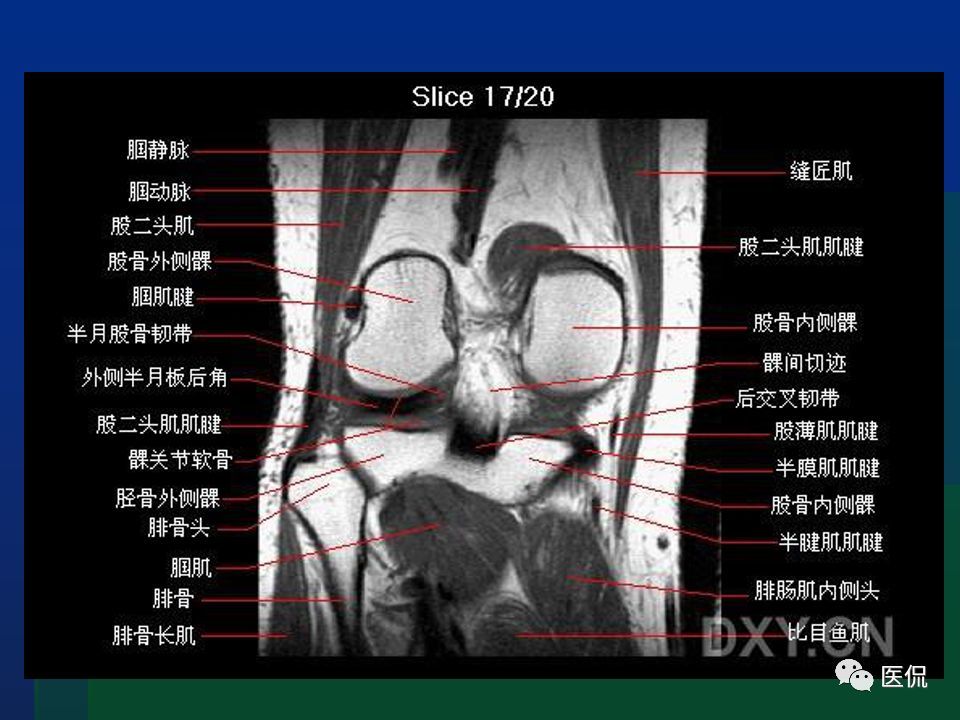

【解剖】膝关节系统解剖图 矢状mri 示意图

膝关节mr解剖ppt

膝关节mri解剖及损伤#医学影像经典ppt